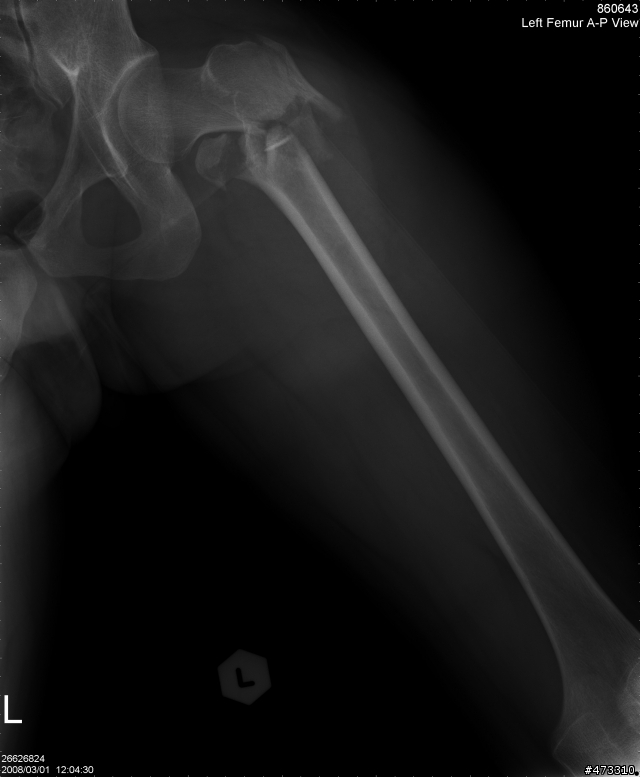

小的我真正重傷害的是在大腿部位

股骨頸與股骨幹本體分離

外加小轉子在復位手術後脫離股股本體跑到坐骨附近

問醫生說阿能處理嗎?他說很難

因為那位置有大量神經叢還有韌帶

大腿總圖

斷裂處特寫

復位手術後兩個月的樣子,有看到一個碎片掉進去坐骨的位置了嗎?